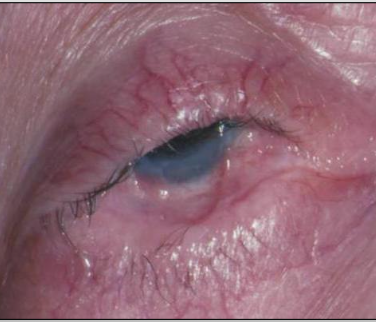

Symblepharons (fibrous scars) along the eye